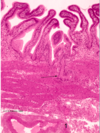

·gall bladder - no muscularis mucosa, submucosa, crypts

From the liver, bile obviously goes through those bile ductules into larger bile ducts that are found in the portal tracts out eventually to the gallbladder. Students confuse the gallbladder with the intestine, or the small intestine. So I’ve put some of the things that are not here, compared to the small intestine.

·There’s not going to be a muscularis mucosa, which you saw in intestine. There’s not going to be a separate submucosa, there’s not going to be crypts, although sometimes there’ll be downgrowths (1) called Aschoff sinuses that are abnormal. And the surface has folds, but these are not really villi.

·And, in addition, if you think about – you’ve seen the abdominal cavity, right? So you know the gallbladder’s smack up against the liver. The side that’s against the liver doesn’t have a mesothelium – it just has an adventitia, but the part that faces the abdominal cavity has a mesothelium out here, and this layer is called the serosa. Again, the complex folds on the surface are not villi. Make sure when you look at the gallbladder that you can distinguish it from the small intestine.

organ?

gallbladder